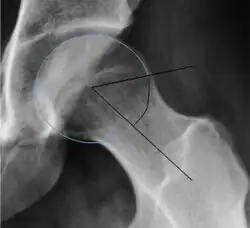

Measurements of impingement on X-ray.[notes 1][20]

Measurement Image Target Normal value

Alpha angle

Measured in 45° Dunn view.

Degree of bulging of the femoral head-neck junction: In normal conditions there is a symmetric concave contour at the junction of the femoral head and neck. Loss of this concavity or bone bulging may lead to cam type impingement. The degree of this deformity can be measured by the alpha angle. Although it can be measured in the cross-lateral view, the 45° Dunn view is considered more sensitive and the frog leg view more specific in determining pathologic values.

• Normal: ≤68° in men, ≤50° in women

• Borderline: 69° to 82° in men, 51° to 56° in women

• Pathological: ≥83° in men and ≥57° in women